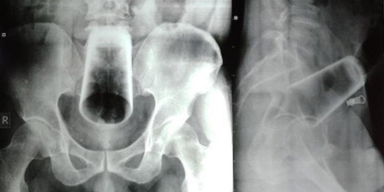

Bei der Untersuchung waren seine Stimmung und sein Verhaltensmuster "normal", und er hatte keine psychiatrischen Erkrankungen. Röntgenaufnahmen zeigten ein Wasserglas in umgekehrter Position im oberen Rektum und im Dickdarm. Die Ärzte lehnten eine Sigmoidoskopie ab - ein Verfahren, das es den Ärzten ermöglicht, mit Hilfe eines flexiblen Schlauches mit Licht in das Innere des Dickdarms zu schauen -, weil sie befürchteten, dass das Glas "beim Entfernen" zerbrechen würde.